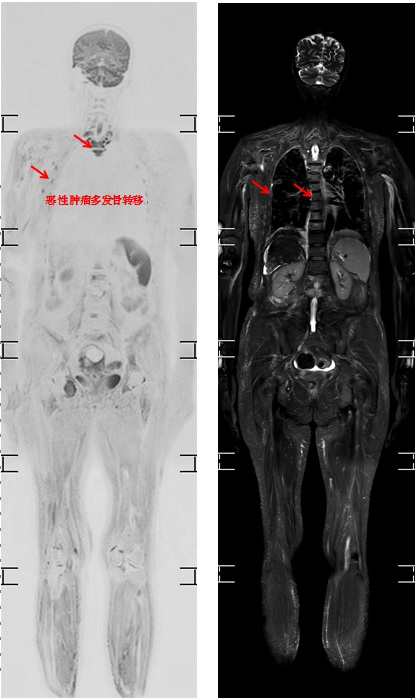

类PET-MRI

一直以来,肿瘤影像学都是整个影像学的重点和难点。如何做到肿瘤的筛查、肿瘤良恶性的鉴别、肿瘤的分期及肿瘤治疗疗效的评估是医学影像学最急需解决的问题,而类PET-MRI大大提高了病变组织--尤其是恶性肿瘤及其转移灶的检出率,对早期发现病灶及为病人的疾病预后提供可靠的检查依据。如:易发生转移的肿瘤病人提供转移预后的诊断价值。

目前国内开展最多的PET成像,对患者而言费用昂贵并伴有电离辐射,因而其临床使用受到了很大限制。类PET-MRI成像与PET相比具有一个极为明显的优势:

1.检查费用远低于PET,因而可以实现在肿瘤病人的常规应用,以及常规体检的应用。

2.类PET-MRI具备了与PET可媲美的恶性肿瘤敏感性和特异性,而且检查方便并且无电离辐射。